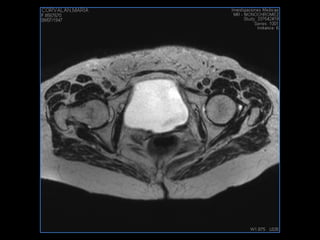

PROTOCOLO pelvis SAG T2, Y FAT SAT (FINOS) AXIAL T1  AX FAT SAT CON   GADOLINIO :  AX T1 Y COR T1 SAT: NO  FASE: RL THK: 3MM  COIL:  GAP: (FACTOR 1.4) 1MM FOV: 40 CM NEX:2 SINCRONIZACION RESPIRATORIA EN 3 O 4 CICLOS ALE